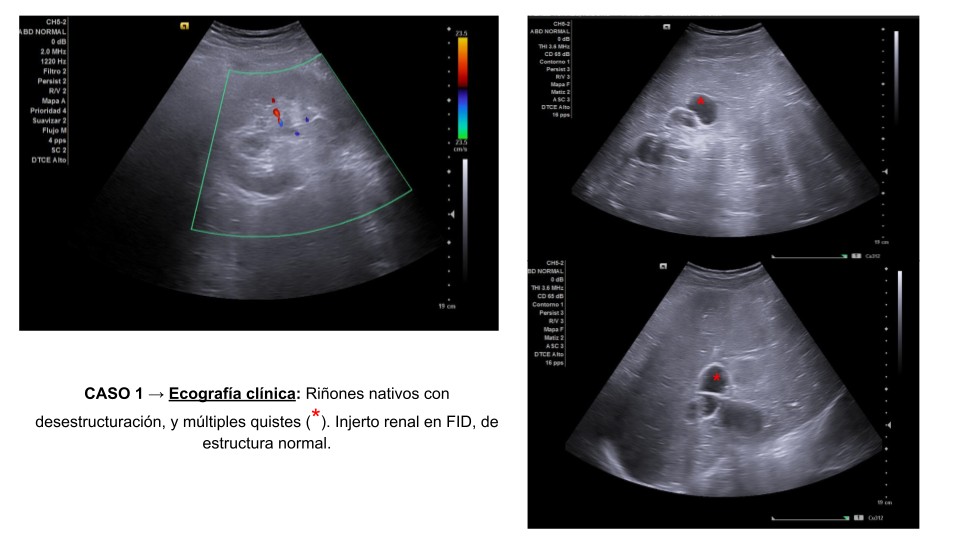

• Caso 1: Riñones nativos con desestructuración, y múltiples quistes. Injerto renal en FID, de estructura normal, con ectasia pielocalicial grado 2, similar a estudios previos.